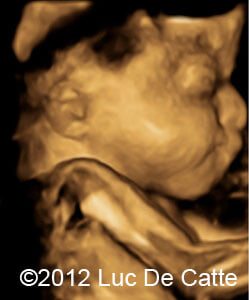

Image 1, 2:  A turricephalic or “tower shaped” skull and frontal bossing

COW_1

COW_1B

• Coronal and sagittal craniosynostosis leading to a turricephalic or “tower shaped” skull

• Prominent forehead (frontal bossing)

The typical craniosyntosis/cloverleaf skull, prominent proptosis and wide great toe suggested Pfeiffer syndrome.